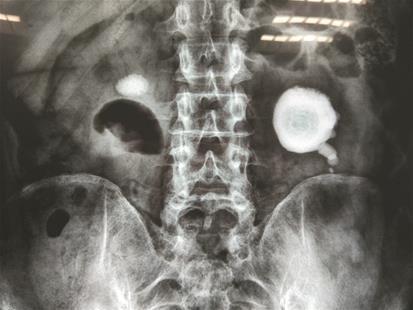

加班頻繁,喜歡喝濃茶,還有“吃茶葉”的喜好,發現結石后還一拖再拖,結果雙腎均被結石“霸占”。近日,恩施的一位先生在武漢京都結石醫院順利完成雙鏡聯合微創保腎取石手術,將撐滿左腎的“荷包蛋”結石及右腎兩公分結石全部取出。

“腎結石長得像荷包蛋,這以后雞蛋是吃不下去了。”在武漢京都結石醫院病房內,該先生跟病友有說有笑。當被問及日常生活習慣,他的回答讓人哭笑不得:“愛喝濃茶,杯子里三分之二都是茶葉,而且特別愛吃泡過的茶葉。加上工作忙,熬夜是常事。”“荷包蛋”大結石被順利取出,出院時這位先生還特地去跟醫生護士一一表達謝意。醫院泌尿結石主任胡換春提醒他說,其腎內巨大草酸鈣成分結石的形成,與其過量喝濃茶有很大關系。而且經常熬夜會影響腎臟排毒,也會增加腎結石形成幾率。合理安排作息,以白開水代替濃茶,少食菠菜、豆制品、咖啡因等富含草酸的食物,可針對性預防草酸鈣結石的再生。